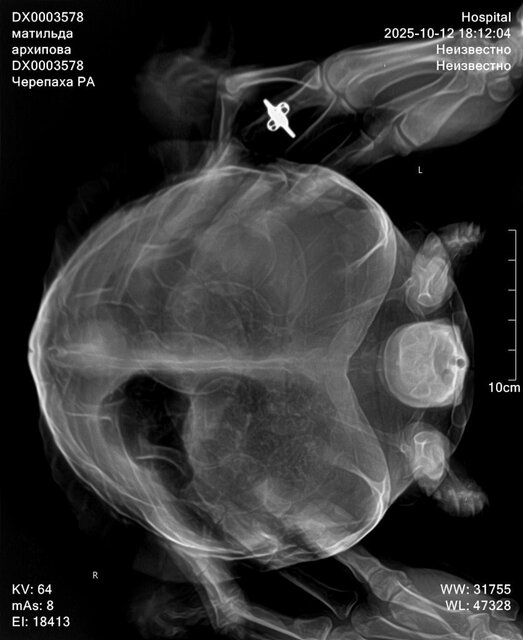

Доброго времени. В результате лечения отёки с лап ушли, с первой "заболевшей" лапы совсем, со второй практически сошли на нет. Доктор на повторном приёме осмотрела, сделала повторный снимок. (На рентгене 11 яиц)  посоветовала дать время на полное восстановление и не применять окситоцин ещё неделю. (Так и поступили) Также она отметила улучшение состояния Матильды: активное поведение при осмотре, во время снимка, её аппетит. На самом деле черепаха вела себя подвижно в кабинете и по дороге домой. Сейчас по прошествии почти 7 дней по прежнему преимущественно спит на одном месте, не активничает в воде (в воде и на поверхности держится хорошо) забирается на остров, сушу и спит. Остаются сомнения и беспокойство по поводу её поведения. Каковы признаки того что животное собирается впасть в спячку? Нет ли таких у неё? Если нет полного восстановления её состояния за две недели -нужно бить тревогу? Или я тороплю события?

Здраствуйте, сегодня обратилась в другую клинику, прогноз не благоприятный, есть признаки почечной недостаточность, есть переизбыток бактерий в кале, есть признаки стоматита в полости рта. Все это очень и очень плохо. Сделали рентген по направлению, к сожалению описание рентгена рентгенологи сделать не могут, без дополнительной платы. Но завтра я уже записана со снимками на повторный приём. Моя огромная ошибка что ограничилась визитами к одному доктору, и потеряла очень много времени. Тк изначально состояние более стабильное хотябы визуально. Завтра получим назначения от главного врача специалиста по экзотам. Покажу им новые снимки. По фото вроде насчитала тоже количество яиц. Но они значительно сместились, вероятно из-за не к месту сделанного окситоцина